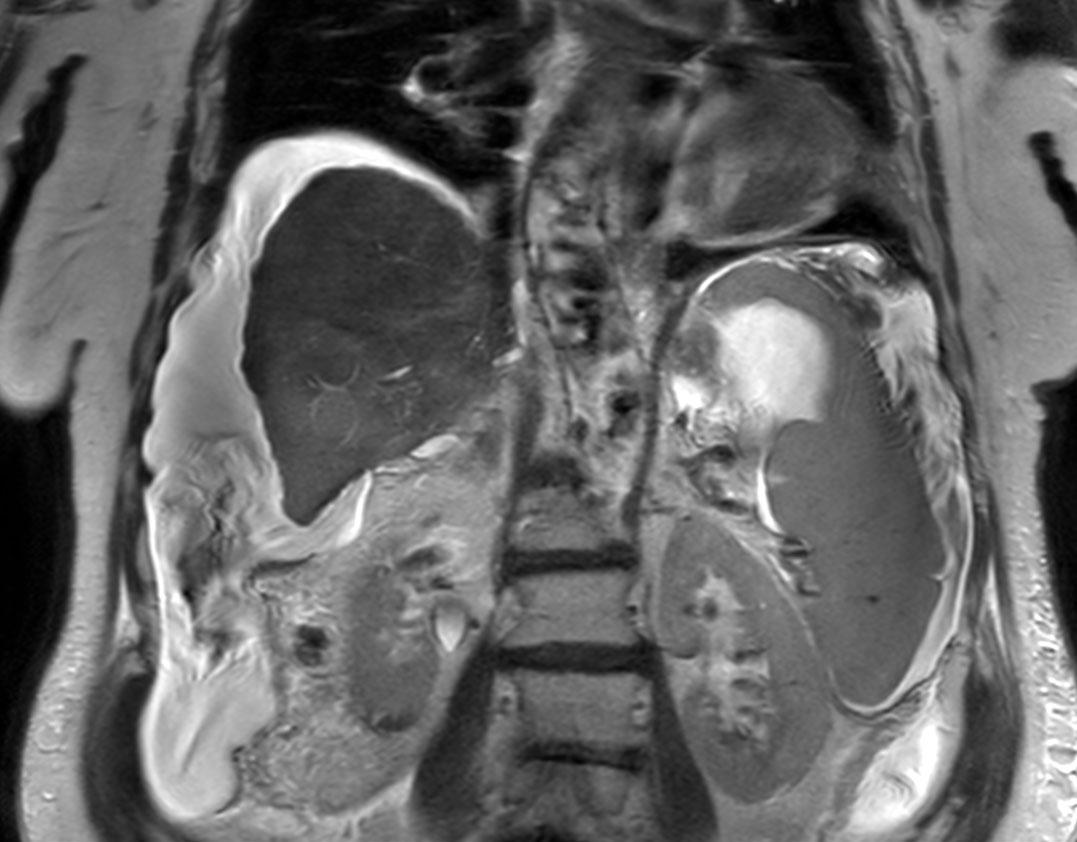

Coronal T2w SSh